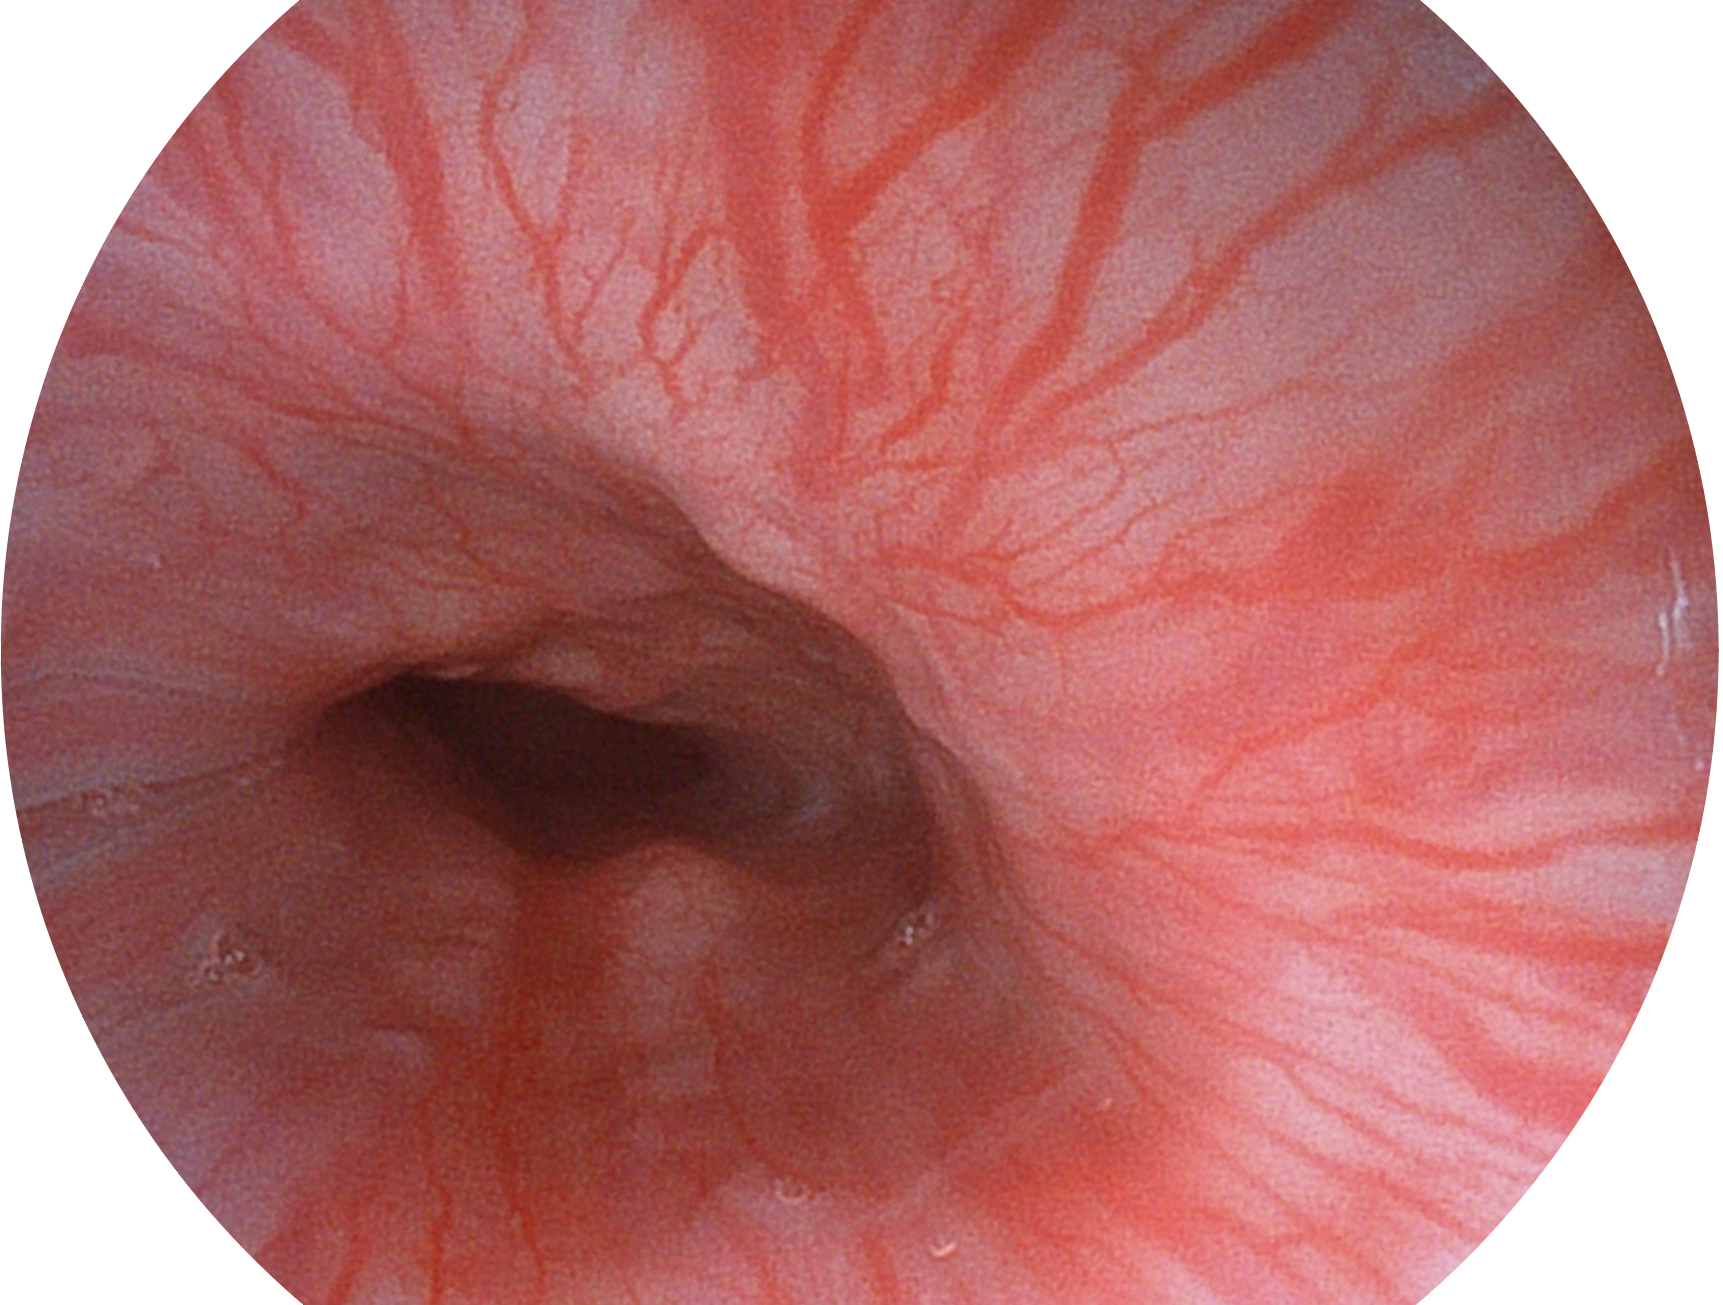

百老汇电子游戏官网新开发的内镜染色技术,主要是基于多波长LED 光源的开发,VLS-55Q 四波长LED 光源是由四个不同颜色的LED光按照相应照明模式所规定的特定发光比例进行合束后形成,合束后形成的照明光的光谱由红光、绿光、蓝光及蓝紫光这四个不同的波段范围构成。具有更高光谱自由度,通过光谱比例的控制,实现了聚谱成像技术,英文全称为“Spectral Focused Imaging, SFI”,缩写为“SFI”和光电复合染色成像技术,英文全称为“Versatile Intelligent Staining Technology, VIST”,缩写为“VIST”。